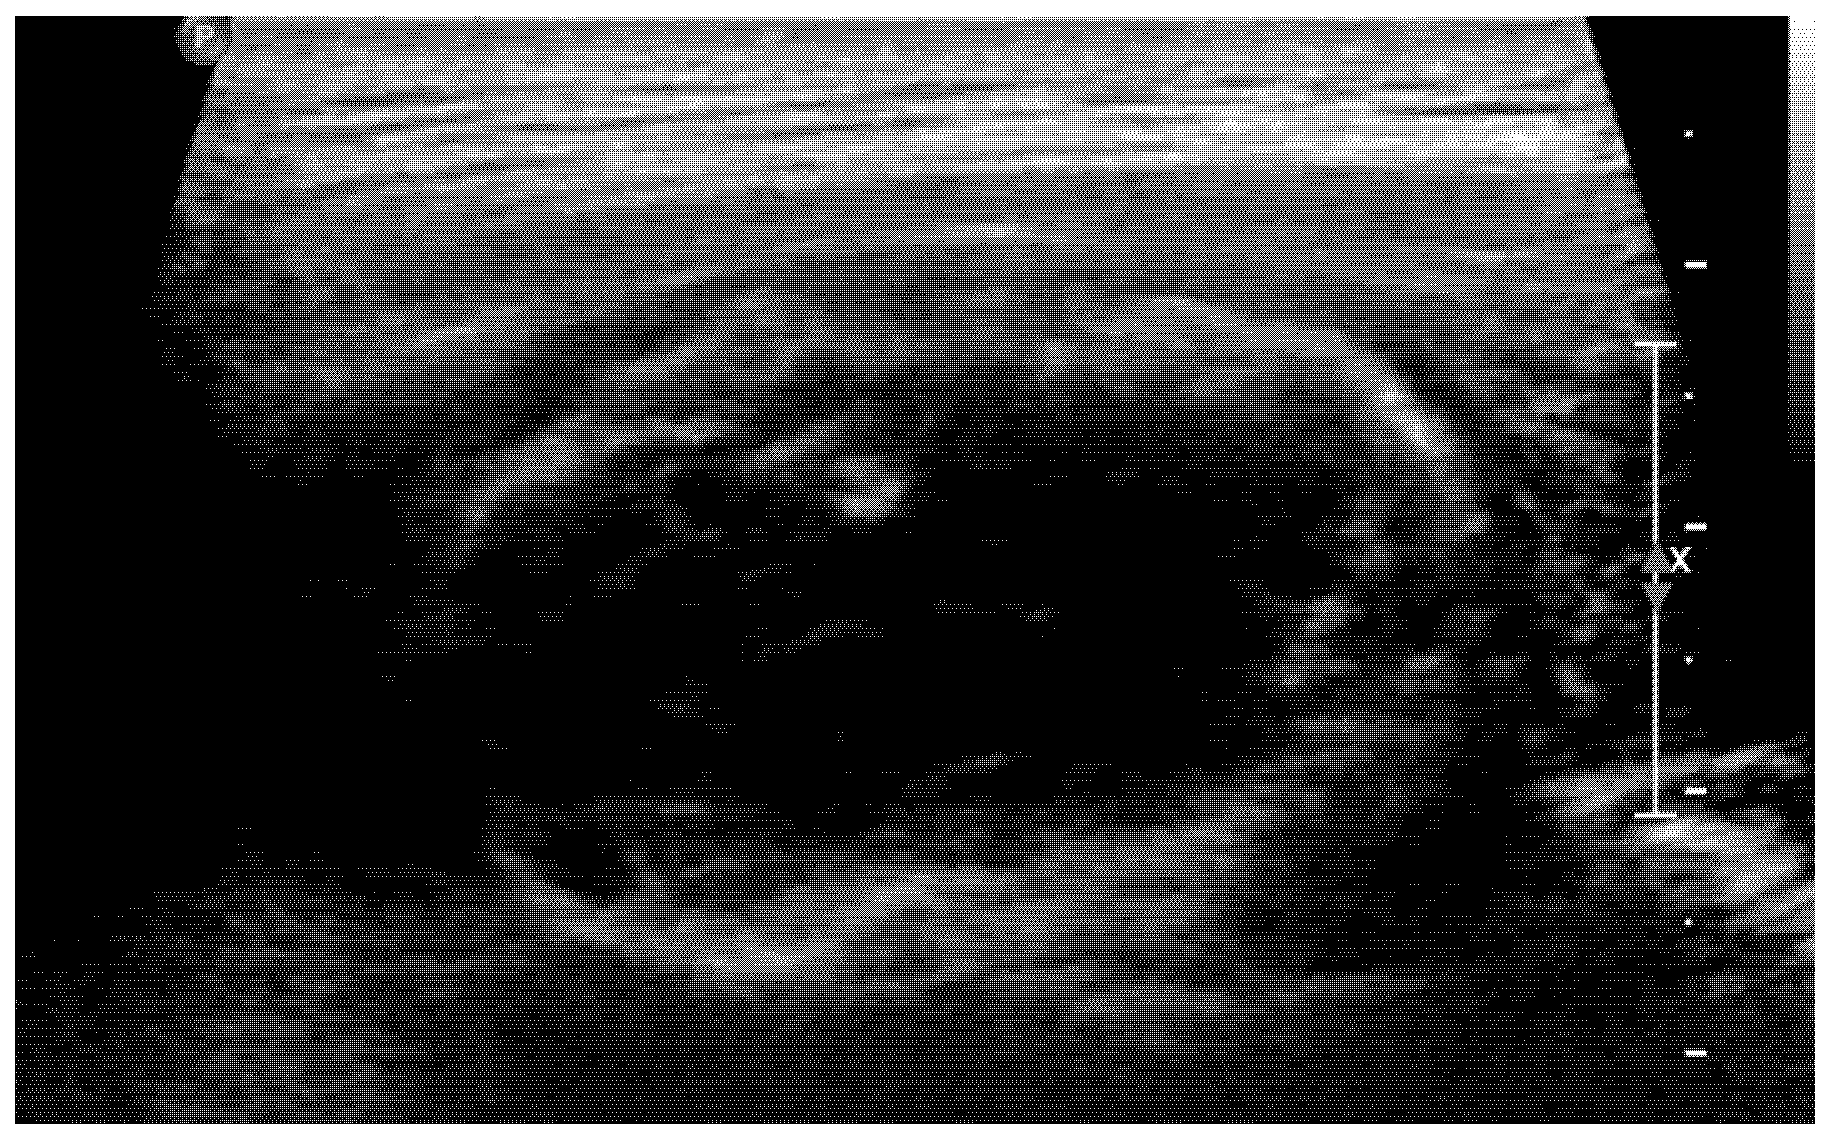

An 18-year-old male student came to our spine center complaining of aggravating right back pain that had started 5 months ago, along with swelling of the mid-thoracic level. At a local hospital, he underwent a chest and heart computed tomography exam for the evaluation of chest and back pain, but there were no abnormal findings on the images (Figure 1). The physician did extracorporeal shock wave therapy at his trunk for the treatment of vague pain about 6 weeks before visiting our institution. He explained that after the extracorporeal shock wave therapy, the back pain worsened, and swelling at the site of pain was found.

Figure 1. Chest CT taken at an outside hospital about 5 months prior to presentation demonstrates no abnormal mass lesion at the paraspinal area of the thoracic spine.